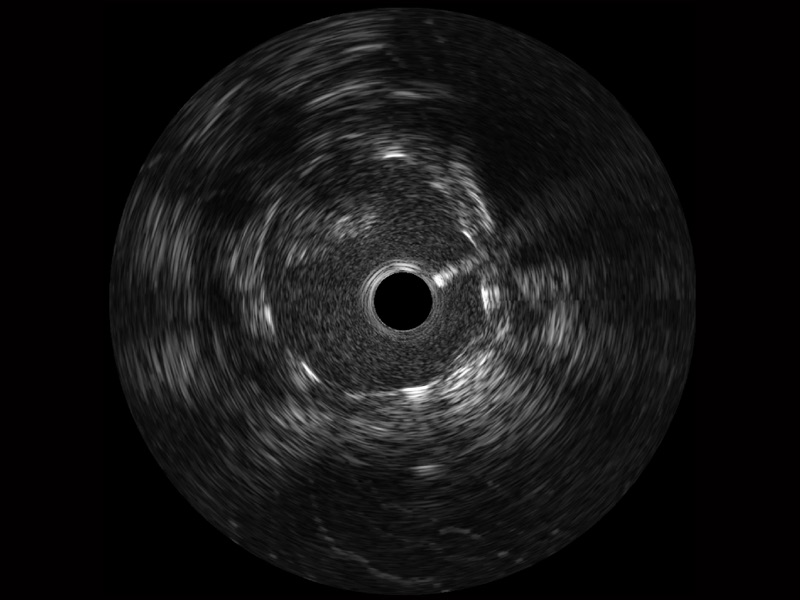

宽频成像,兼具高分辨力和更大穿透深度

太阳成tyc7111cc官网超宽频成像技术覆盖20-80MHz1或20-90MHz2频率范围, 提供优异的分辨力同时也保证充足的穿透深度

1.SonoSound? Crystal导管对比传统IVUS导管成像,太阳成tyc7111cc官网宽频IVUS图像的近场支架梁显影更细腻,远场中膜外血管仍清晰可辨,兼顾远中近,兼顾分辨力与穿透深度